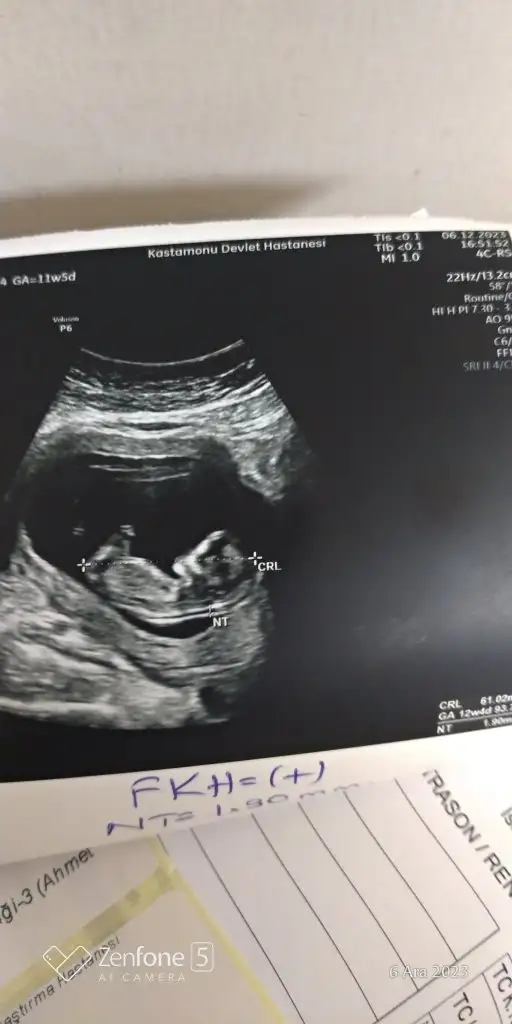

Oyyy eskiden böyle fotolar görünce patatese benzetirdim ama şimdi bakınca gözlerim doluyorMerhaba analyanalr yada tahmin etmek isteyenler bakabilirmiEki Görüntüle 3347449